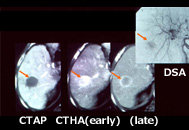

- 画像診断:腹部超音波検査(エコー検査)、CT/MRI、血管造影(カテーテル検査)

肝臓がんの画像診断

総合画像診断により正確な診断ができ、治療法の選択に有用である